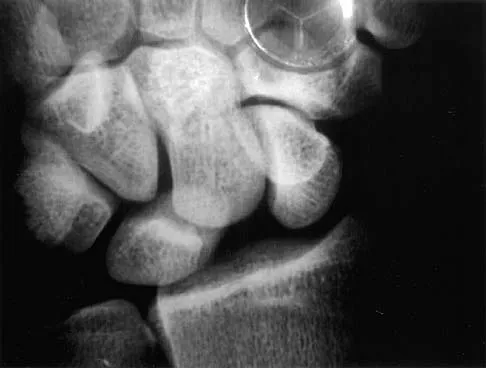

A 17-year-old high school football player reports wrist pain after being tackled. Radiographs are shown in Figures 22a through 22c. What is the recommended intervention?

Explanation